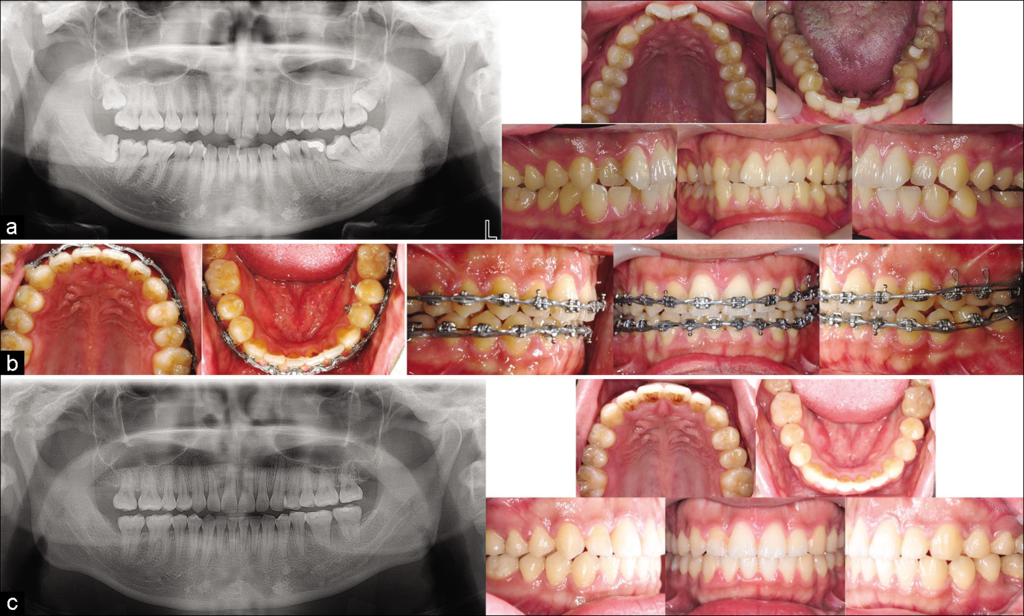

Les agénésies dentaires, définies comme l’absence congénitale d’une ou plusieurs dents, posent des défis cliniques complexes nécessitant une approche multidisciplinaire. Ce document explore de manière détaillée les options thérapeutiques pour le traitement des agénésies, en mettant l’accent sur les incisives latérales supérieures et les deuxièmes prémolaires inférieures. Les choix thérapeutiques dépendent de nombreux facteurs, incluant la morphologie dentaire, les relations occlusales, les conditions parodontales, et les considérations socio-économiques. Les traitements orthodontiques et prothétiques sont souvent combinés pour obtenir des résultats fonctionnels et esthétiques optimaux.

Le traitement des agénésies bilatérales des incisives latérales supérieures repose sur deux grandes options thérapeutiques, chacune présentant des variantes. Une concertation étroite entre l’orthodontiste et le dentiste prothésiste est essentielle pour déterminer la meilleure approche en fonction des caractéristiques cliniques du patient.

Traitement Orthodontique

Conservation ou Augmentation des Espaces

- Traitement précoce : Vise à établir des relations de classe I molaires nettes, souvent à l’aide d’un fil élastique buccal (FEB) sur bagues.

- Traitement tardif : Repositionnement des canines en classe I et fermeture des diastèmes inter-incisifs à l’aide d’un dispositif multi-attaches.

Fermeture des Espaces

- Traitement précoce : Favorise la migration mésiale des canines et des premières molaires permanentes par :

- Extraction précoce des incisives et canines temporaires.

- Extraction des deuxièmes molaires temporaires (14, 24) ou meulage de leurs faces proximales (mésiales et distales).

- Traitement tardif :

- Coronoplastie : Réalisée avant le traitement orthodontique pour ajuster la forme des dents.

- Dispositif multi-attaches : Indispensable pour un alignement précis.

- Masque de Delaire : Utilisé si nécessaire pour corriger les décalages squelettiques.

- Finition esthétique : Reconstitution des angles des dents à l’aide de composites chargés.

- Rééquilibration occlusale : Meulage de la cuspide palatine de la première prémolaire supérieure (en position de canine) ou utilisation d’un onlay palatin.